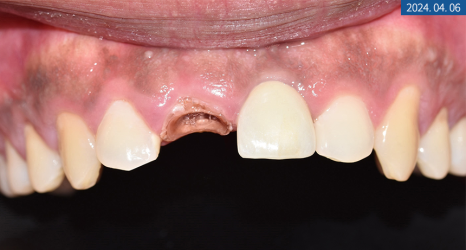

상담을 할 때 환자분께서

부드러운 음식만 주로 먹게 될 만큼

앞니가 많이 불편해요.

라고 하셨는데요.

X-ray 상 앞니 손상과 치근 염증이

심하다는 결과를 봐서는 발치가 필요해 보였으며

좌측 하악 어금니도 뿌리 밑에 염증이 생겨

치아 보존이 힘든 상황이었습니다.

그만큼 치아 강직과 만성 복합치주염으로 인한

난발치 상황이었죠.

우측도 파열돼있었지만

우선 치주 치료를 하면서 지켜봐도

좋을 것 같다는 판단이 들었습니다.